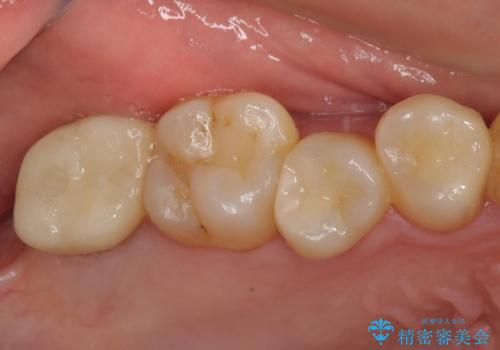

放置したむし歯 抜歯後にインプラントで補綴治療